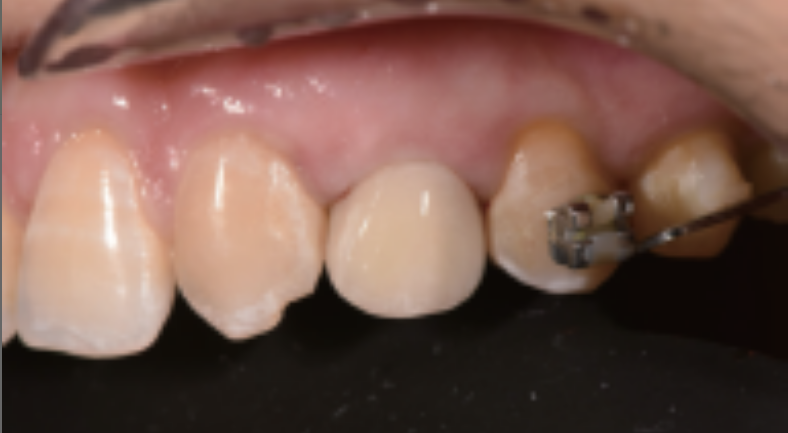

主诉“左上乳尖牙滞留18年”,1年前正畸后保持阶段,近日松动,前来寻求修复方案。

全口牙周情况良好,左上后牙正畸保持托槽固定,63滞留,松动(++),牙槽窝周围牙槽骨完整,

X线显示根尖周未见低密度影像,根尖区充足骨量;22先天缺失,23在22位置异位萌出,23与21邻接良好。

结果4个月后复诊,取出临时冠及个性化基台,袖口形态良好,牙龈塑形效果佳,重新开窗式个性化取模,更换全瓷基台,全瓷冠粘接修复,完成最终修复,患者满意。